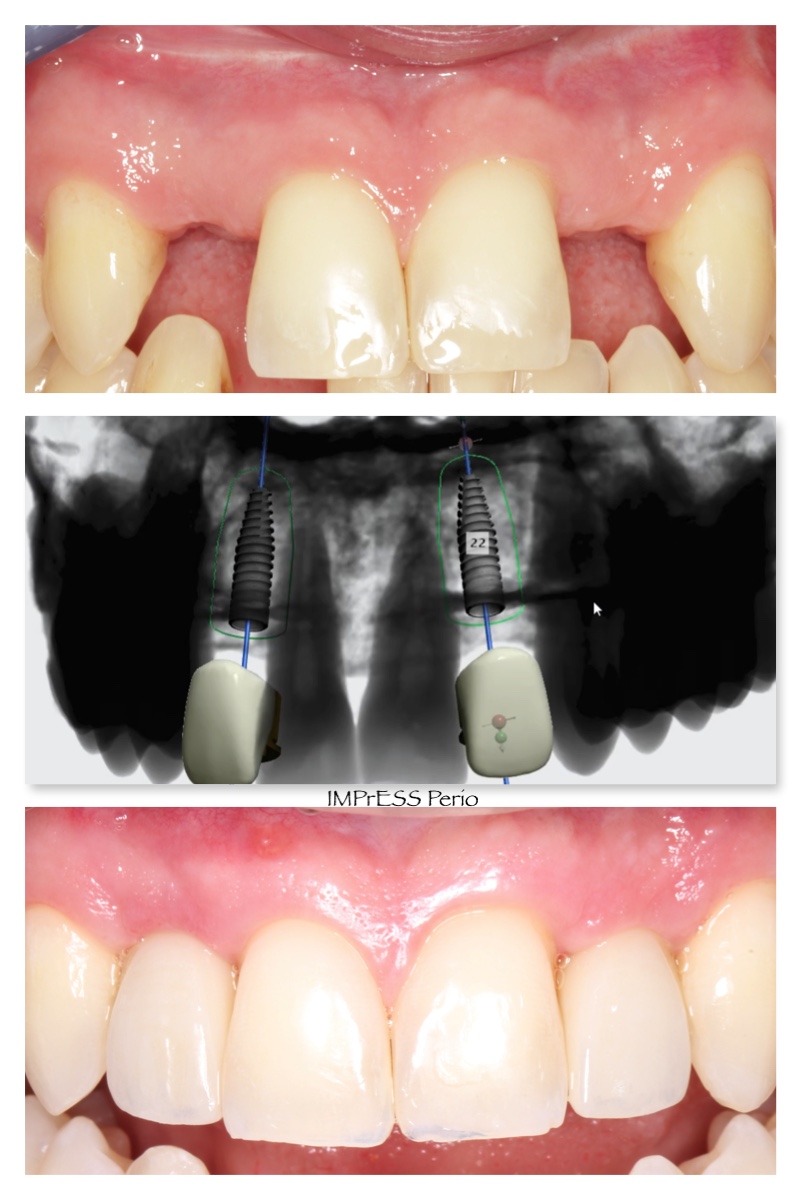

Before & Afters of Dental Implant Patients

Complete Dental Implant Cases Gallery

We use digital innovations to digitally plan implant placement to receive the most predictable outcome through:

• Create radiographic and surgical templates from guided surgery software

• Nerve detection, segmentation, and implant placement for prosthetic-driven implant planning with guided surgery software.

• Precision surgical guided placement using restorative-driven three-dimensional imaging and planning allows for more predictable surgical placement.

• High surface digital impression scanning and CAD/ CAM milling allows for precision design and modeling for improved accuracy of both the abutment and restorations. Combining these digital technologies allows us to plan and treat the patient in a more efficient manner with more predictable results.

General Disclaimer: The results in the photographs are examples only and do not imply any certainty of the result of a procedure, and all outcomes are subject to the circumstances of the individual patient.